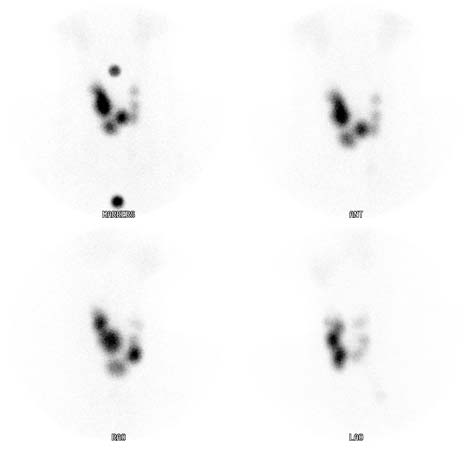

Esta es una exploración de la tiroides que muestra múltiples áreas irregulares redondeadas y brillantes dentro de la tiroides. Representa un bocio 'multinodular'.

Nota: Las imágenes se muestra para fines ilustrativos. No trate de sacar conclusiones comparando esta imagen con otras en el sitio. Solamente los radiólogos calificados deben interpretar las imágenes.